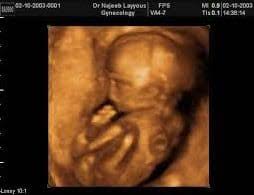

شكل الجنين في الشهر الخامس البنت

شكل الجنين الولد في السونار في الشهر الرابع الساعة 25